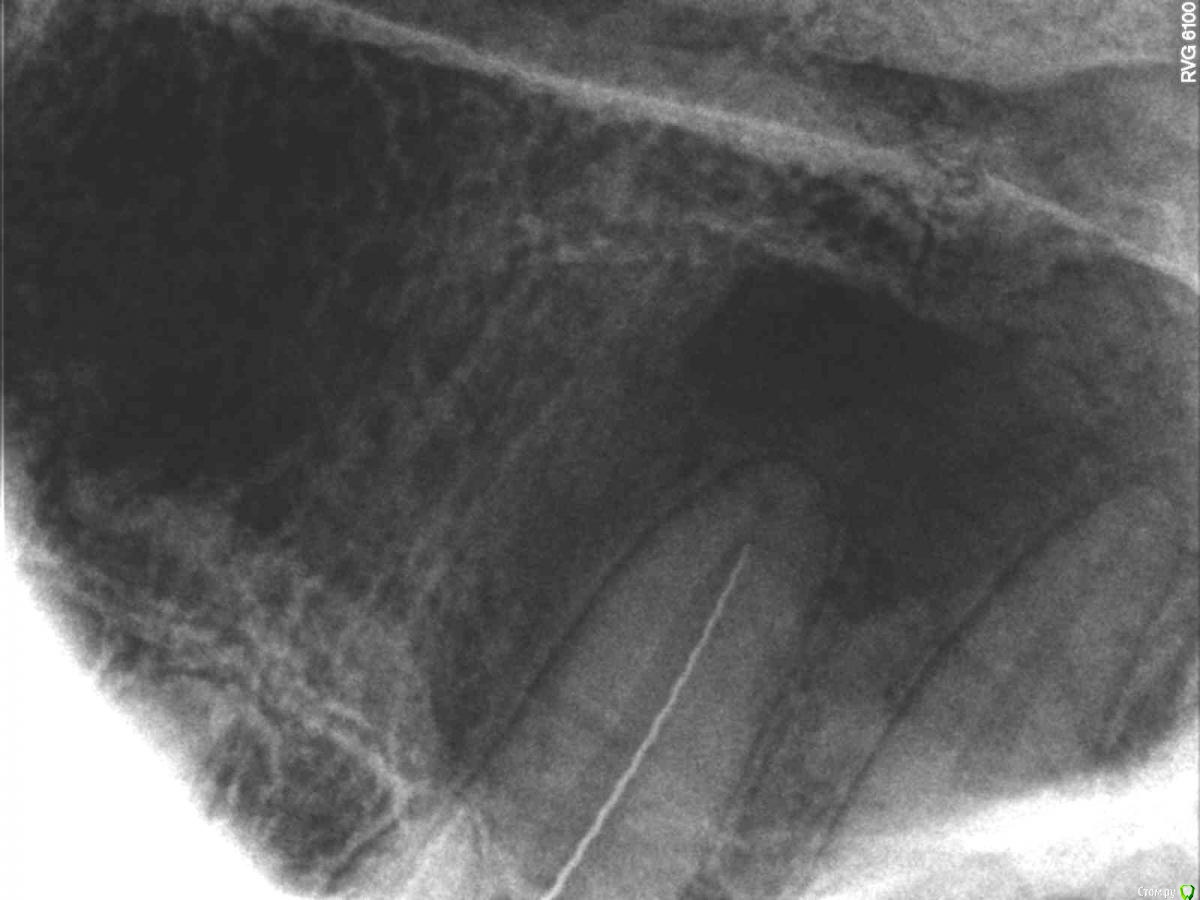

SolnceSamara Опубликовано 24 октября, 2015 Поделиться Опубликовано 24 октября, 2015 почернела старая пломба в давно пролеченной шестерке (сверху). Врач заменила пломбу но зуб болел при надавливании, заменили пломбу повторно-все равно осталась боль, сменила врача-снова сменили пломбу-снова болит, решили депульпировать-снова вынули пломбу, поставили временную-неделю проходила с временной-через неделю окончательно депульпировали, поставили постоянную. Сначало поболело 3 дня, и вроде прошло, хотя остался дискомфорт при надавливании. Прошло 3 недели, боль усилилась, теперь болит не только при надавливании иногда просто звеняще-ноющее ощущение нарастает. Пью нимесил. Посоветуйте что делать-что не так? Снимки прилагаю-делали на протяжении всйх операций (до и после).Разьяснение по снимкам :R1-29/08/15R2,R3-25/09/15R4-R7-28/09/15 Ссылка на комментарий

red_butler Опубликовано 24 октября, 2015 Поделиться Опубликовано 24 октября, 2015 Коллеги поправят, но выглядит как пломбирование одиночным штифтом. Возможно пропущен четвертый канал. Нужна ревизия корневых каналов. 2 Ссылка на комментарий

DmitrySH Опубликовано 24 октября, 2015 Поделиться Опубликовано 24 октября, 2015 Коллеги поправят, но выглядит как пломбирование одиночным штифтом. Возможно пропущен четвертый канал. Нужна ревизия корневых каналов. Все верно. Ссылка на комментарий